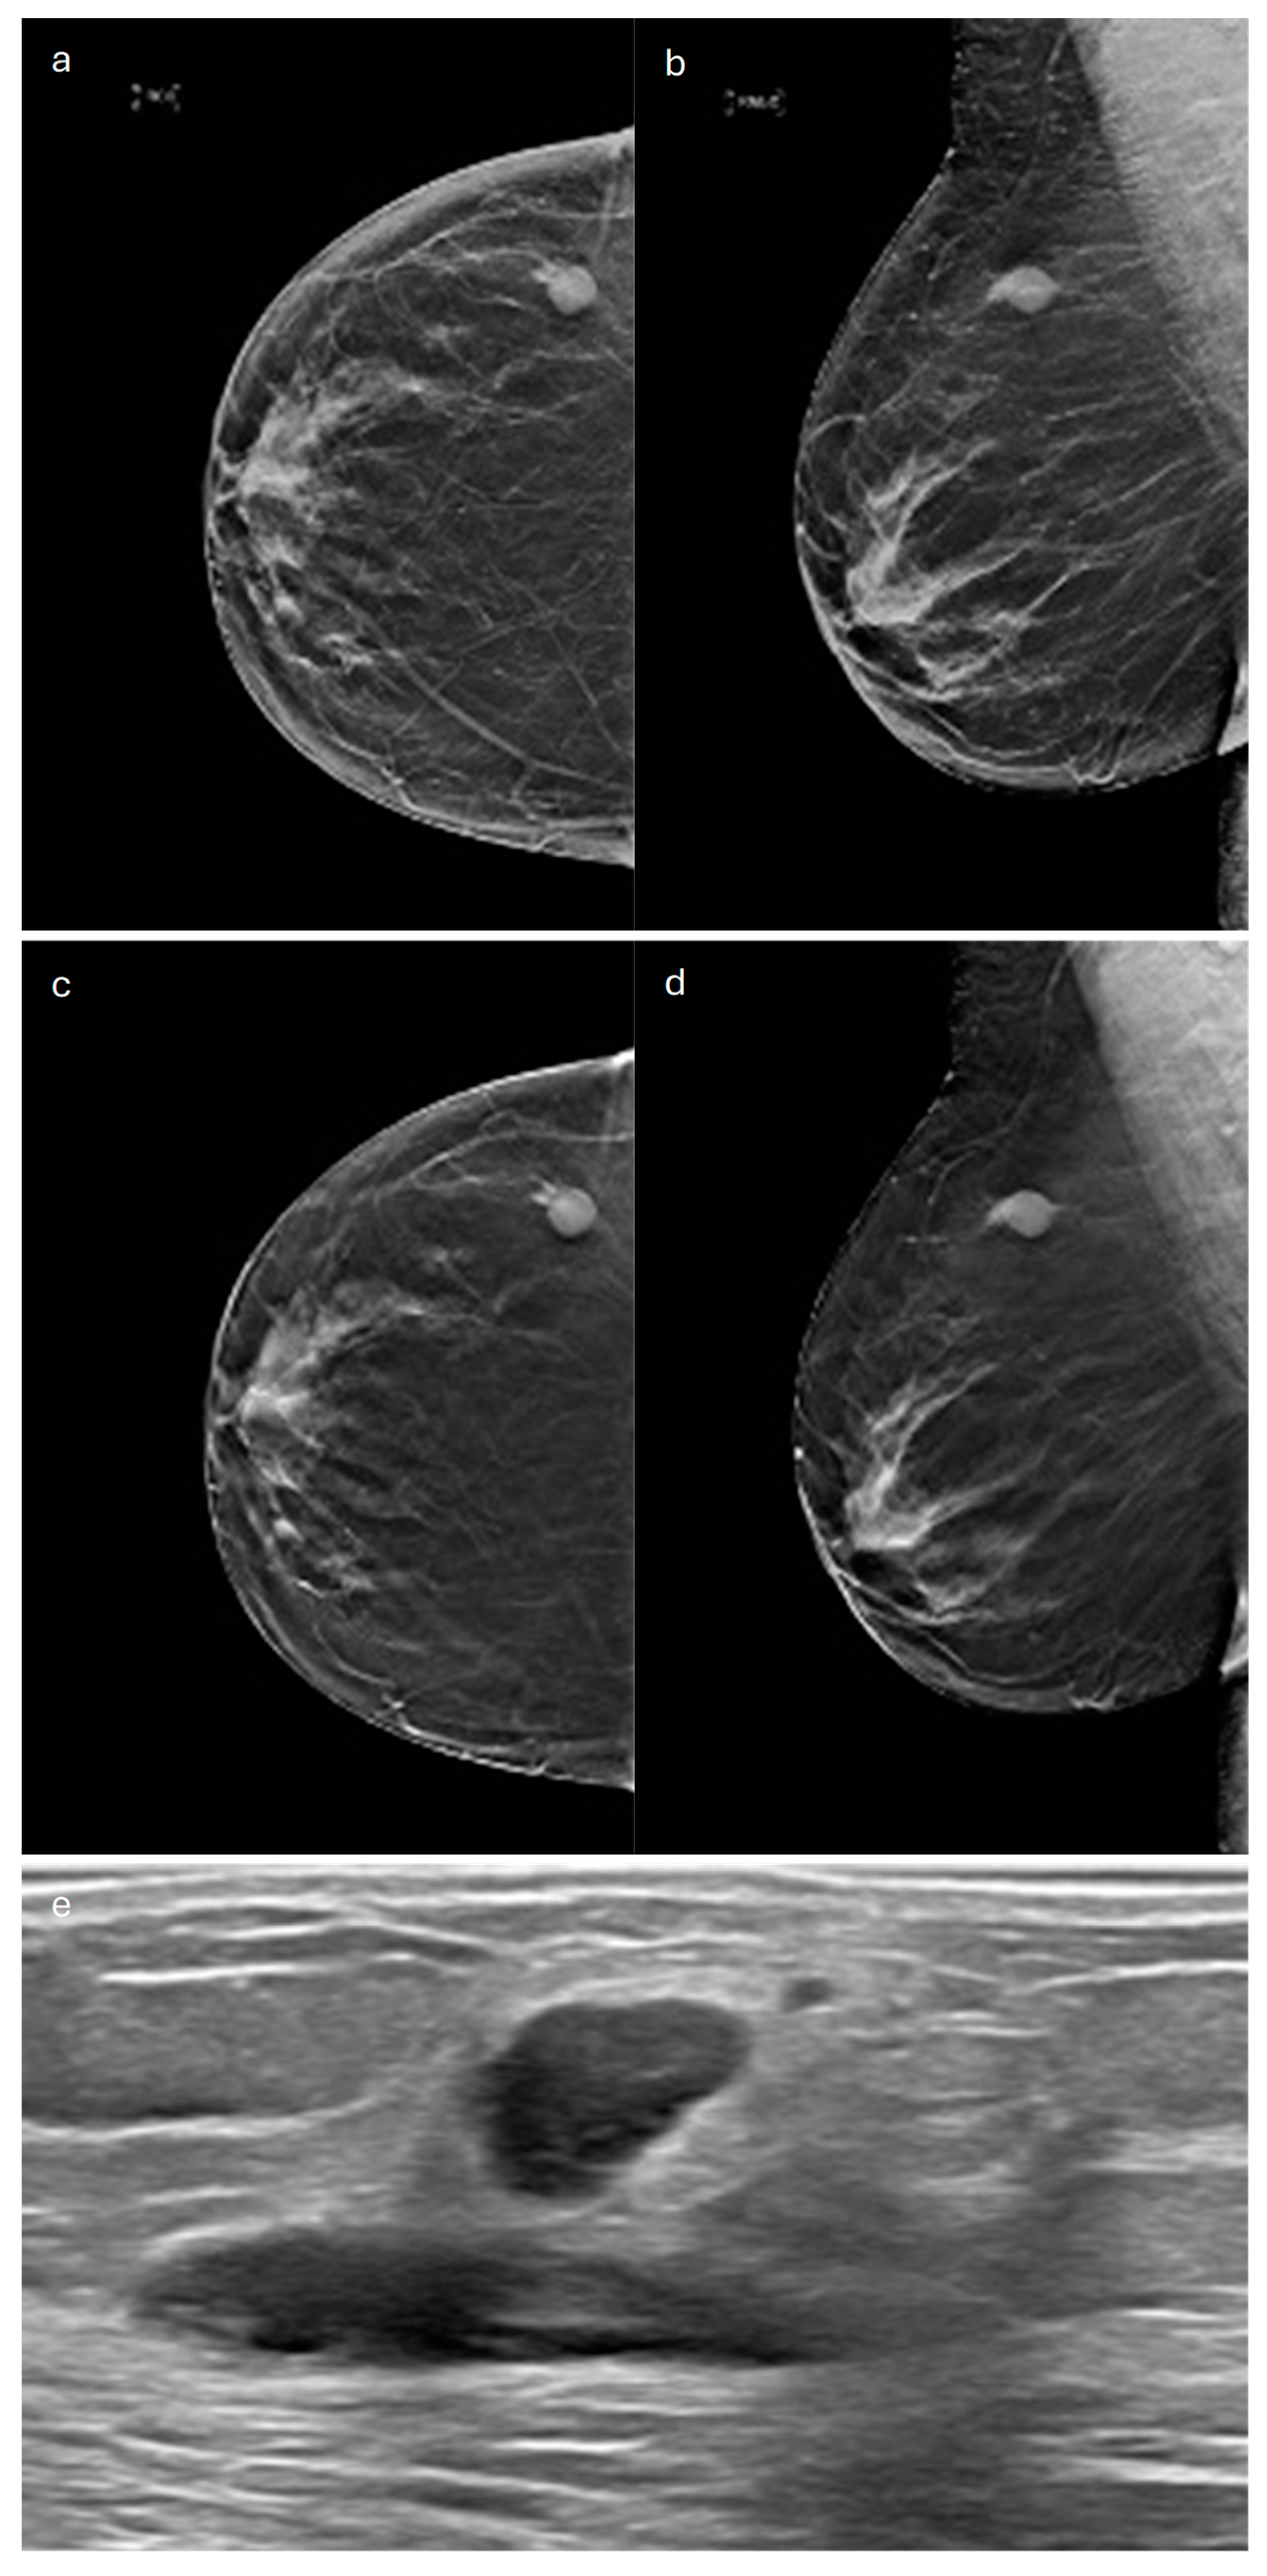

3. Tubular